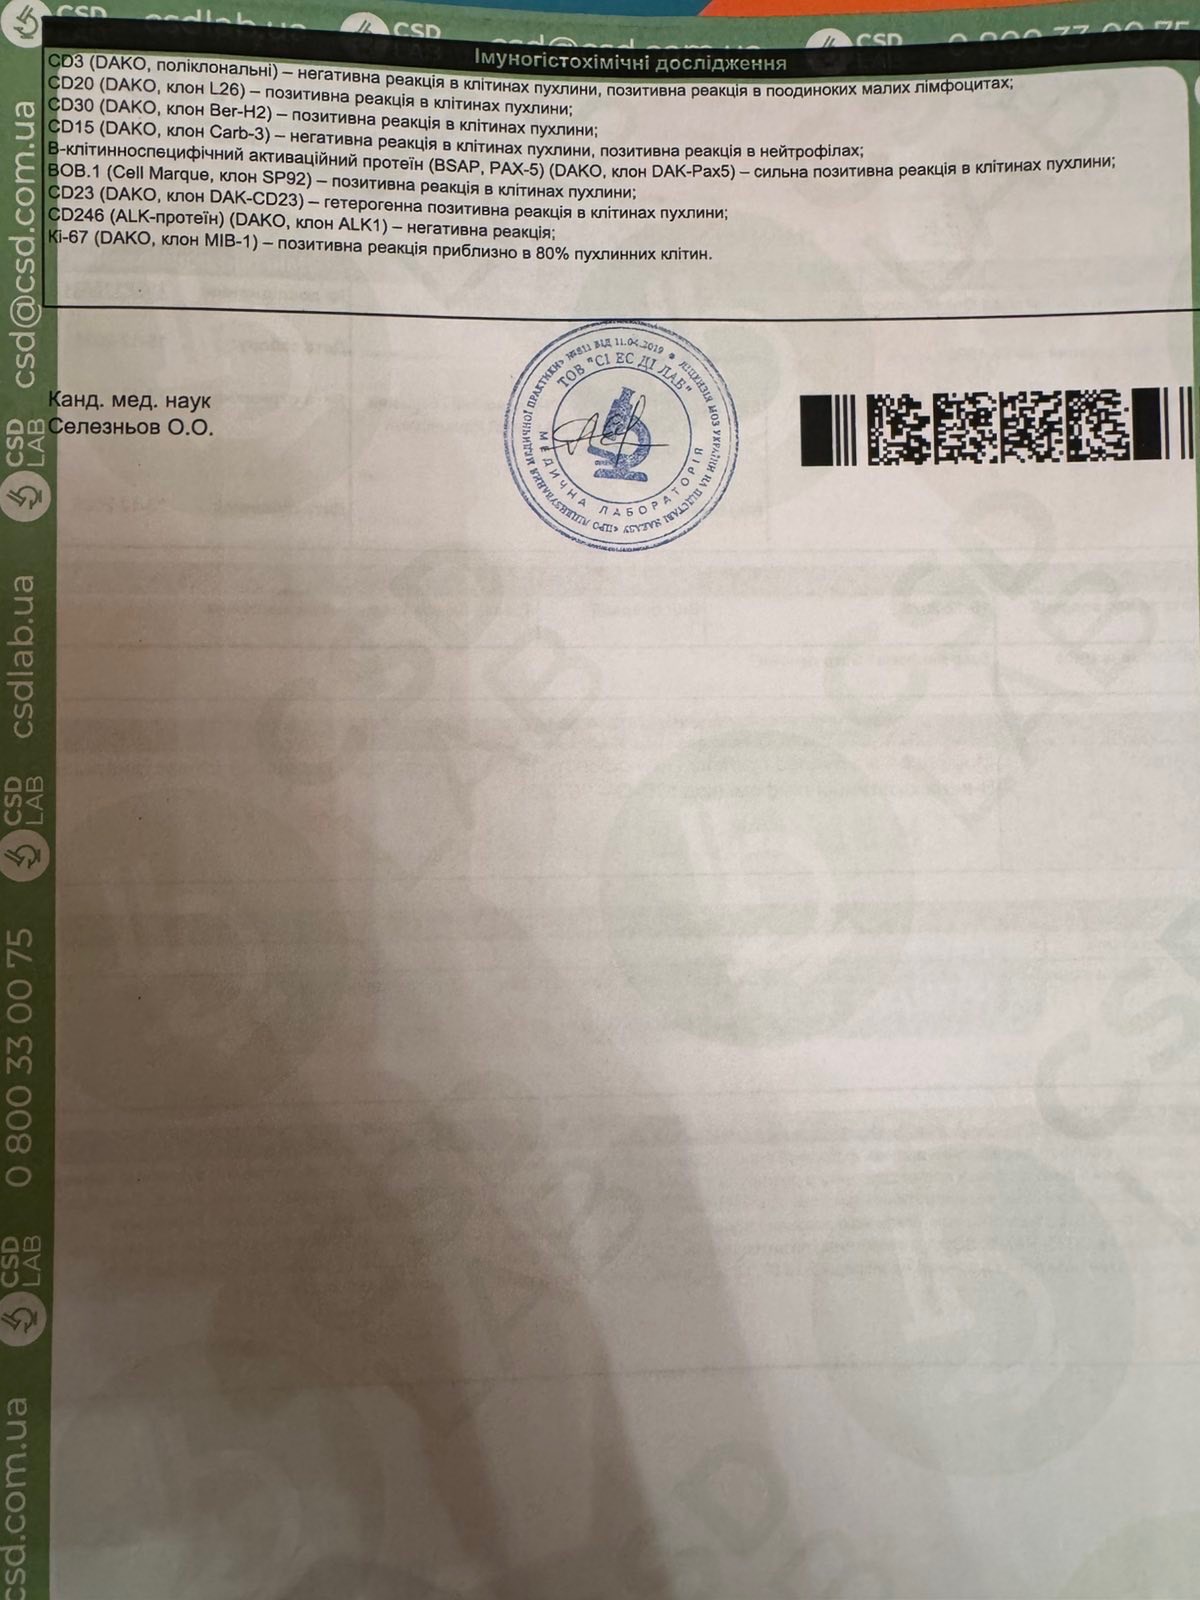

Oleksandr was diagnosed with Primary Mediastinal Large B-Cell Lymphoma, an aggressive but treatable form of cancer. The diagnosis came as a complete shock, especially given his young age and the fact that he was just starting a new chapter of life as a husband and soon-to-be father.

Олександру поставили діагноз — первинна медіастинальна великоклітинна В-клітинна лімфома — агресивна, але лікувальна форма раку. Цей діагноз став повним шоком, особливо з огляду на його молодий вік і те, що він лише починав новий етап життя як чоловік і майбутній батько.